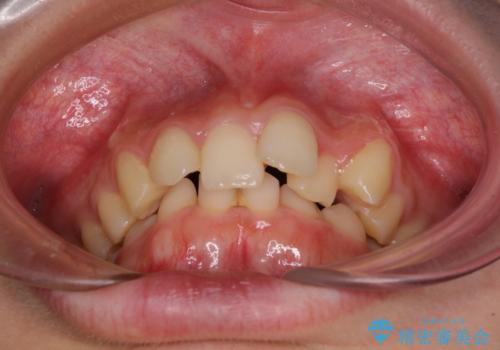

- 下顎前歯が欠損しており、前歯がデコボコとなっている歯並びを気にして来院された患者様です。

下顎の左右側切歯2本が欠損しており、上顎歯列がデコボコとなっている状態でした。

下顎歯列に対して上顎歯列が相対的に大きくなっているため、デコボコとなっているだけでなく、下顎前歯が見えなくなるくらいのディープバイトにもなっていました。